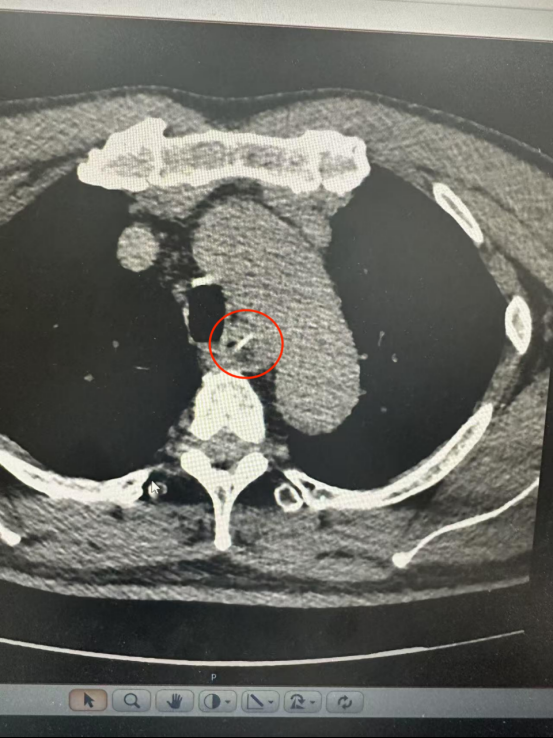

CT扫描显示,一根约25毫米长的鱼骨卡在食管中部,两端靠近食管壁外缘和主动脉弓内侧。主动脉是人体最大的动脉,鱼骨处于非常危险的位置。

根据三维CT重建结果,鱼骨接近主动脉弓,但没有穿透主动脉和食管的全层。尖端垂直于ta主动脉正切,呈“1”字形。